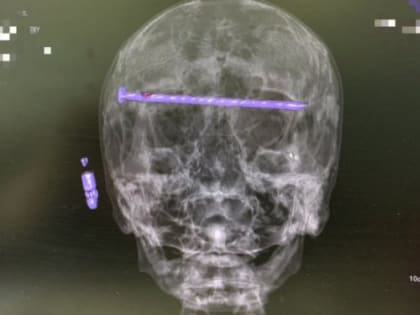

Хирурги Нижнего Тагила успешно провели сложнейшую операцию

78-летнему пациенту извлекли 15-сантиметровый гвоздь из головы.